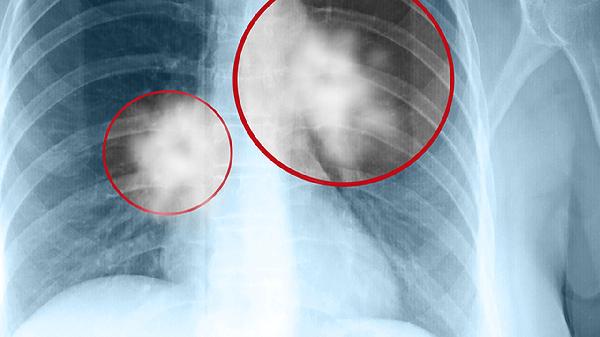

2、形态特征:良性肿瘤通常边界清晰,形态规则,呈圆形或椭圆形,表面光滑;恶性肿瘤边界模糊,形态不规则,可能呈分叶状或毛刺状,表面凹凸不平。影像学检查中,良性肿瘤的钙化现象较为常见,而恶性肿瘤的钙化较少,且可能伴有空洞或坏死区域。